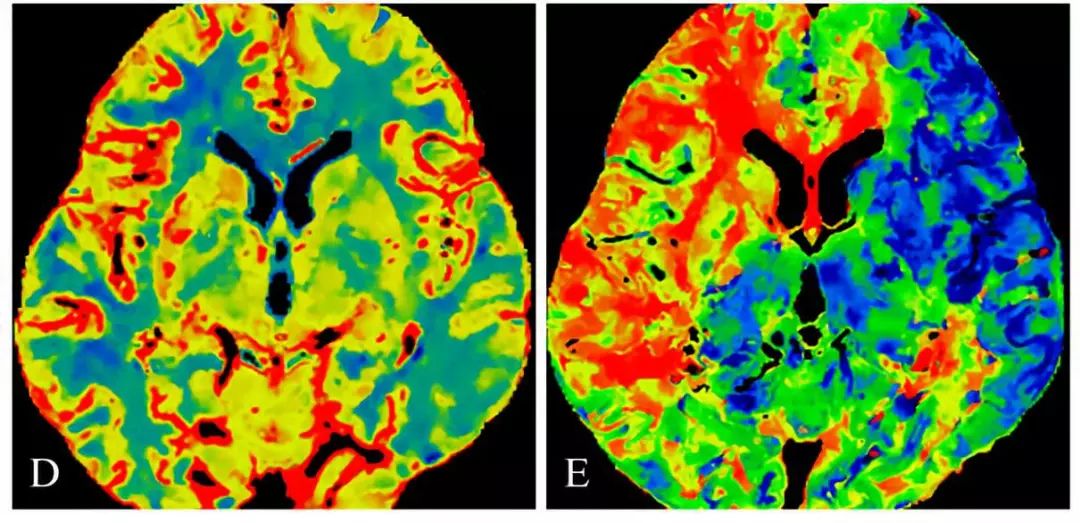

CTP:显示颅内灌注显示右侧半球低灌注

CTP